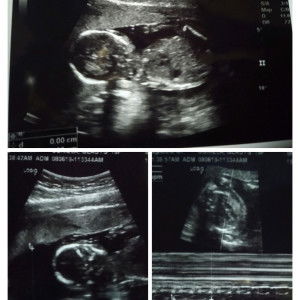

Hello ilang weeks na kayo Kailan due date niyo!?

Dec 30 here